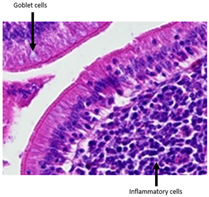

| Observations | Picture 40× | Picture 400× | |

|---|---|---|---|

| Samples from the CTL group | Inflammatory cellular infiltrates in the mucosa (with the participation of heterophils) Single mitotic figures in crypt epithelial cells Connective tissue hyperplasia |  |  |

| |||

| SNCE group | Scant infiltration of inflammatory cells in the mucosa (with the participation of heterophils) and the formation of individual lymphatic nodules Numerous goblet cells/heavily filled with mucus Vesicular nuclei of intestinal crypt epithelial cells; numerous mitotic figures |  |  |

|